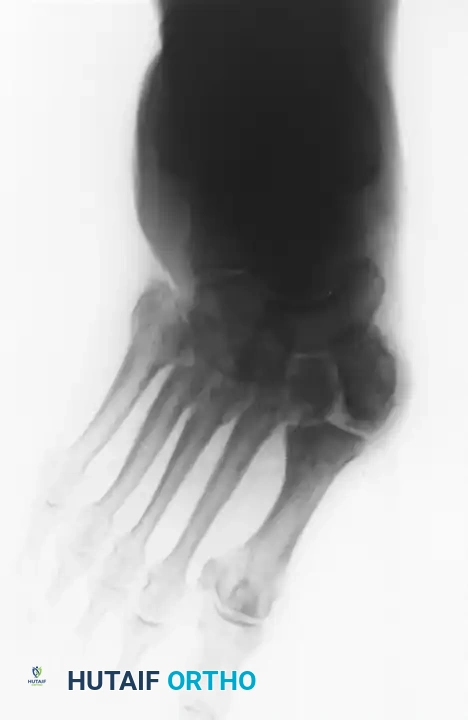

صورة شعاعية توضح انهيار مفاصل ليزفرانك وتشوه القدم

تعتبر الأشعة السينية الأداة الأساسية لتقييم حالة العظام. في المراحل المبكرة، قد تبدو الأشعة السينية طبيعية، ولكن مع تقدم المرض، تظهر علامات تفتت العظام، وخلع المفاصل، وتكون عظام جديدة بشكل غير طبيعي.